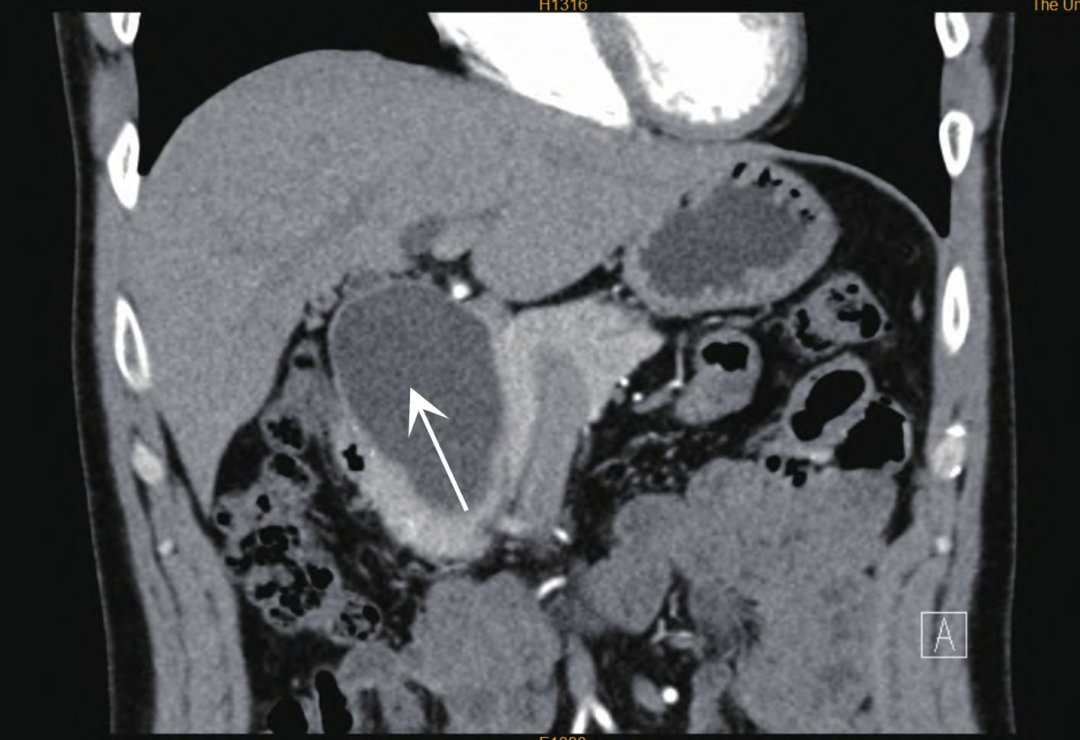

患者因发现胆总管囊肿20 d就诊,入院前2周偶有腹胀伴恶心,无呕吐,无发热,无腹泻及腹痛,无胸痛,无消瘦,无皮疹。腹部无压痛及反跳痛,Murphy征为阴性,肝、脾、肋下未扪及,移动性浊音为阴性。血常规检查显示,白细胞计数8.06×109/L,血红蛋白159 g/L,血小板计数216×109/L,嗜酸性粒细胞0.26×109/L。肝功能检查显示,丙氨酸氨基转移酶13.7 U/L,天门冬氨酸氨基转移酶17.6 U/L,清蛋白45.1 g/L,总胆红素9.6 μmol/L,直接胆红素3.9 μmol/L。血淀粉酶74 U/L,血糖正常,人类免疫缺陷病毒(HIV)抗原及抗体均为阴性,免疫球蛋白(Ig)A 2.53 g/L。腹部CT检查显示肝门下-胰头区较大囊性灶,考虑胆总管囊肿(Ⅰ型),最大径为49 mm×49 mm×77 mm,胰头部胰管略受压扩张(图1),入院后行胆总管囊肿切除及胆肠吻合术。

注:箭头处为胆总管囊肿。

图1 上腹部增强CT(矢状位)